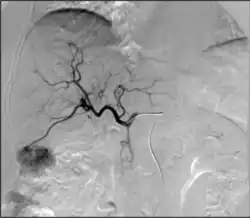

TACE

• Can be performed in different ways:

• Conventional transarterial chemoembolization (cTACE): Injection of lipiodol with high dose chemotherapy with or without microparticles directly into the tumor-feeding arteries.[66]

• Drug eluting bead transarterial chemoembolization (DEB-TACE): delivery of microparticles that are themselves loaded with the chemotherapy agent—typically doxorubicin or irinotecan.

• Transarterial chemoembolization (TACE): Injection of a chemotherapy agent often with microparticles through a catheter into arteries feeding a tumor that both delivers chemotherapy and blocks the blood supply to the tumor to cause cell death[65]